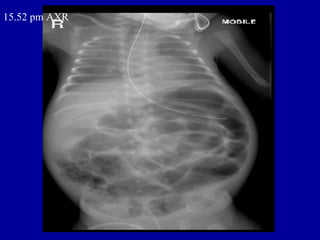

15.52 pm AXR

ORIGINAL REPORT • HISTORY • ? sepsis. Growing prem. Abdominal distension. • REPORT • CXR - MOBILE SUPINE AP • Compared with CXR from 14/12/2004. • NG tube is again noted. There is now bilateral perihilar peribronchial thickening. • Cardiac size is unremarkable. • The intestinal loops remained gaseously distended though faecal matter is seen within • the colon. There is a lack of rectal air through a catheter is seen in the lower • pelvic cavity.